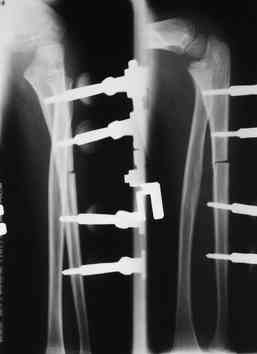

Артротомия, иссечение рубцов, остатков кольцевидной связки. На

проксимальный отдел локтевой кости стержневой аппарат (рекомендуют

Compact II выпущеный Stryker Howmedica, но за неименеем...),

остеотомия проксимального отдела локтевой кости, вправление головки

лучевой кости, замыкание аппарата, проверка стабильности головки

лучевой кости в движении, ушивание без пластики кольцевидной связки.

1 подвывих головки лучевой кости в положении супинации-

через 2 недели после операции- под ЭОП: аппарат разблокирован,

повторное вправление головки, стабилизация аппарата.

2 По снятии аппарата через 2 мес после операции рефрактура в месте

остеотомии(на фоне активного ротационного движения)- под контролем ЭОП выполнен

интрамедуллярный остеосинтез TEN. Положение головки луча стабильное.